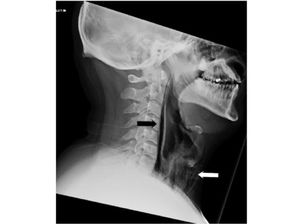

Seorang pria mengalami kondisi tak terduga akibat menahan bersin. Ia mengalami sakit parah di bagian lehernya hingga robekan di tenggorokan.